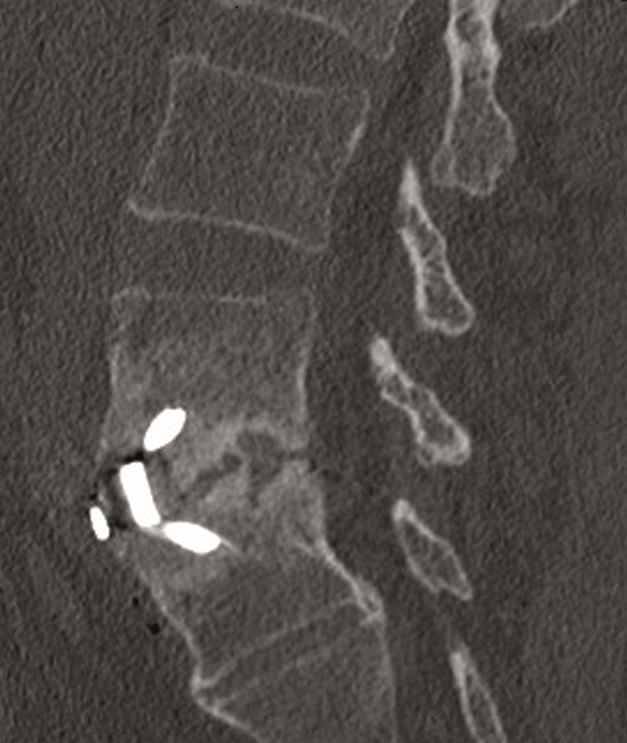

Case 4 : ALIF L4-L5 non union

A 40-year-old man 5 years after ALIF L4-L5 using SynFix with axial low back pain. The CT scan shows locked pseudarthrosis (Fig 17). Nonoperative treatment failed. The treatment option was bilateral Facet Wedge at L4-L5.

A less invasive approach was used with Insight Retractor using the bilateral Facet Wedge. No bone graft. X-ray follow-up after 3 months and CT assessment after 6 months (Fig 18-19).